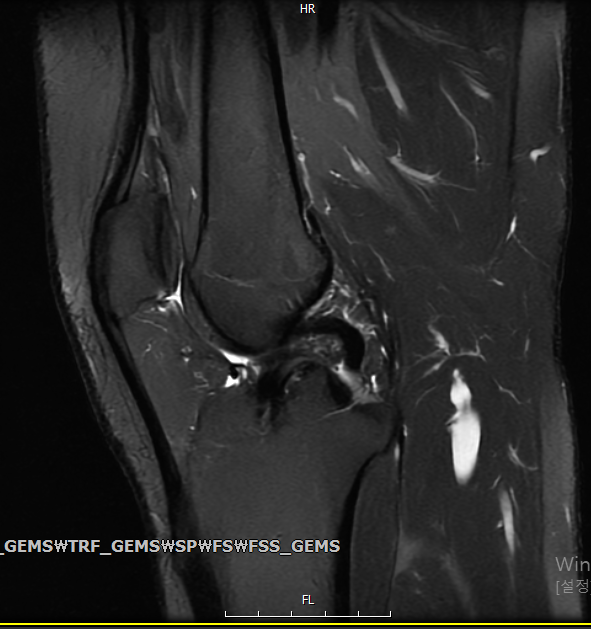

Mri를 찍었는데… 연골연화증인가요?

병원을 2번이나 번갈아가며 돌았는데도 별 의견 없이 진통제만 주셔서.... 믿을수가 없어 제가 그동안 공부 좀 해왔는데요, 관절 사이에 원래 저렇게 하얀색으로 차있으면 염증이라고 봤거든요. 슬개골부터 관절강까지 차있는거로 보아 무릎 연골 연화증인것 같은데... 심한 편인가요..? 프롤로 주사 맞으면 괜찮아지겠죠...?

• 1번 째 사진

현재 MRI영상만으로는 연골연화증을 의심할 수는 없으며, 관절사이의 물 또한 정상적인 관절액 정도로 볼 수 있을 것 같습니다.

올려준 MRI 사진에서 관절 사이에 하얗게 보이는건 물 입니다. 양도 많지 않고 정상적으로도 소량의 물은 있을수 있습니다.

연골연화증은 아닙니다. 애초에 올려주신 사진은 연골연화증을 판단하는데 쓰이는 사진도 아니네요. MRI가 쉬워보여도 제대로 판독하기까지 이론에 대한 공부와 수많은 케이스를 경험해보아야 합니다.

병원에서 그동안 별 의견없이 진통제만 주신 이유는 무릎 MRI사진에서 특이소견이 없어서인 것 같네요. 진통제 잘 드시면 될 것같습니다.